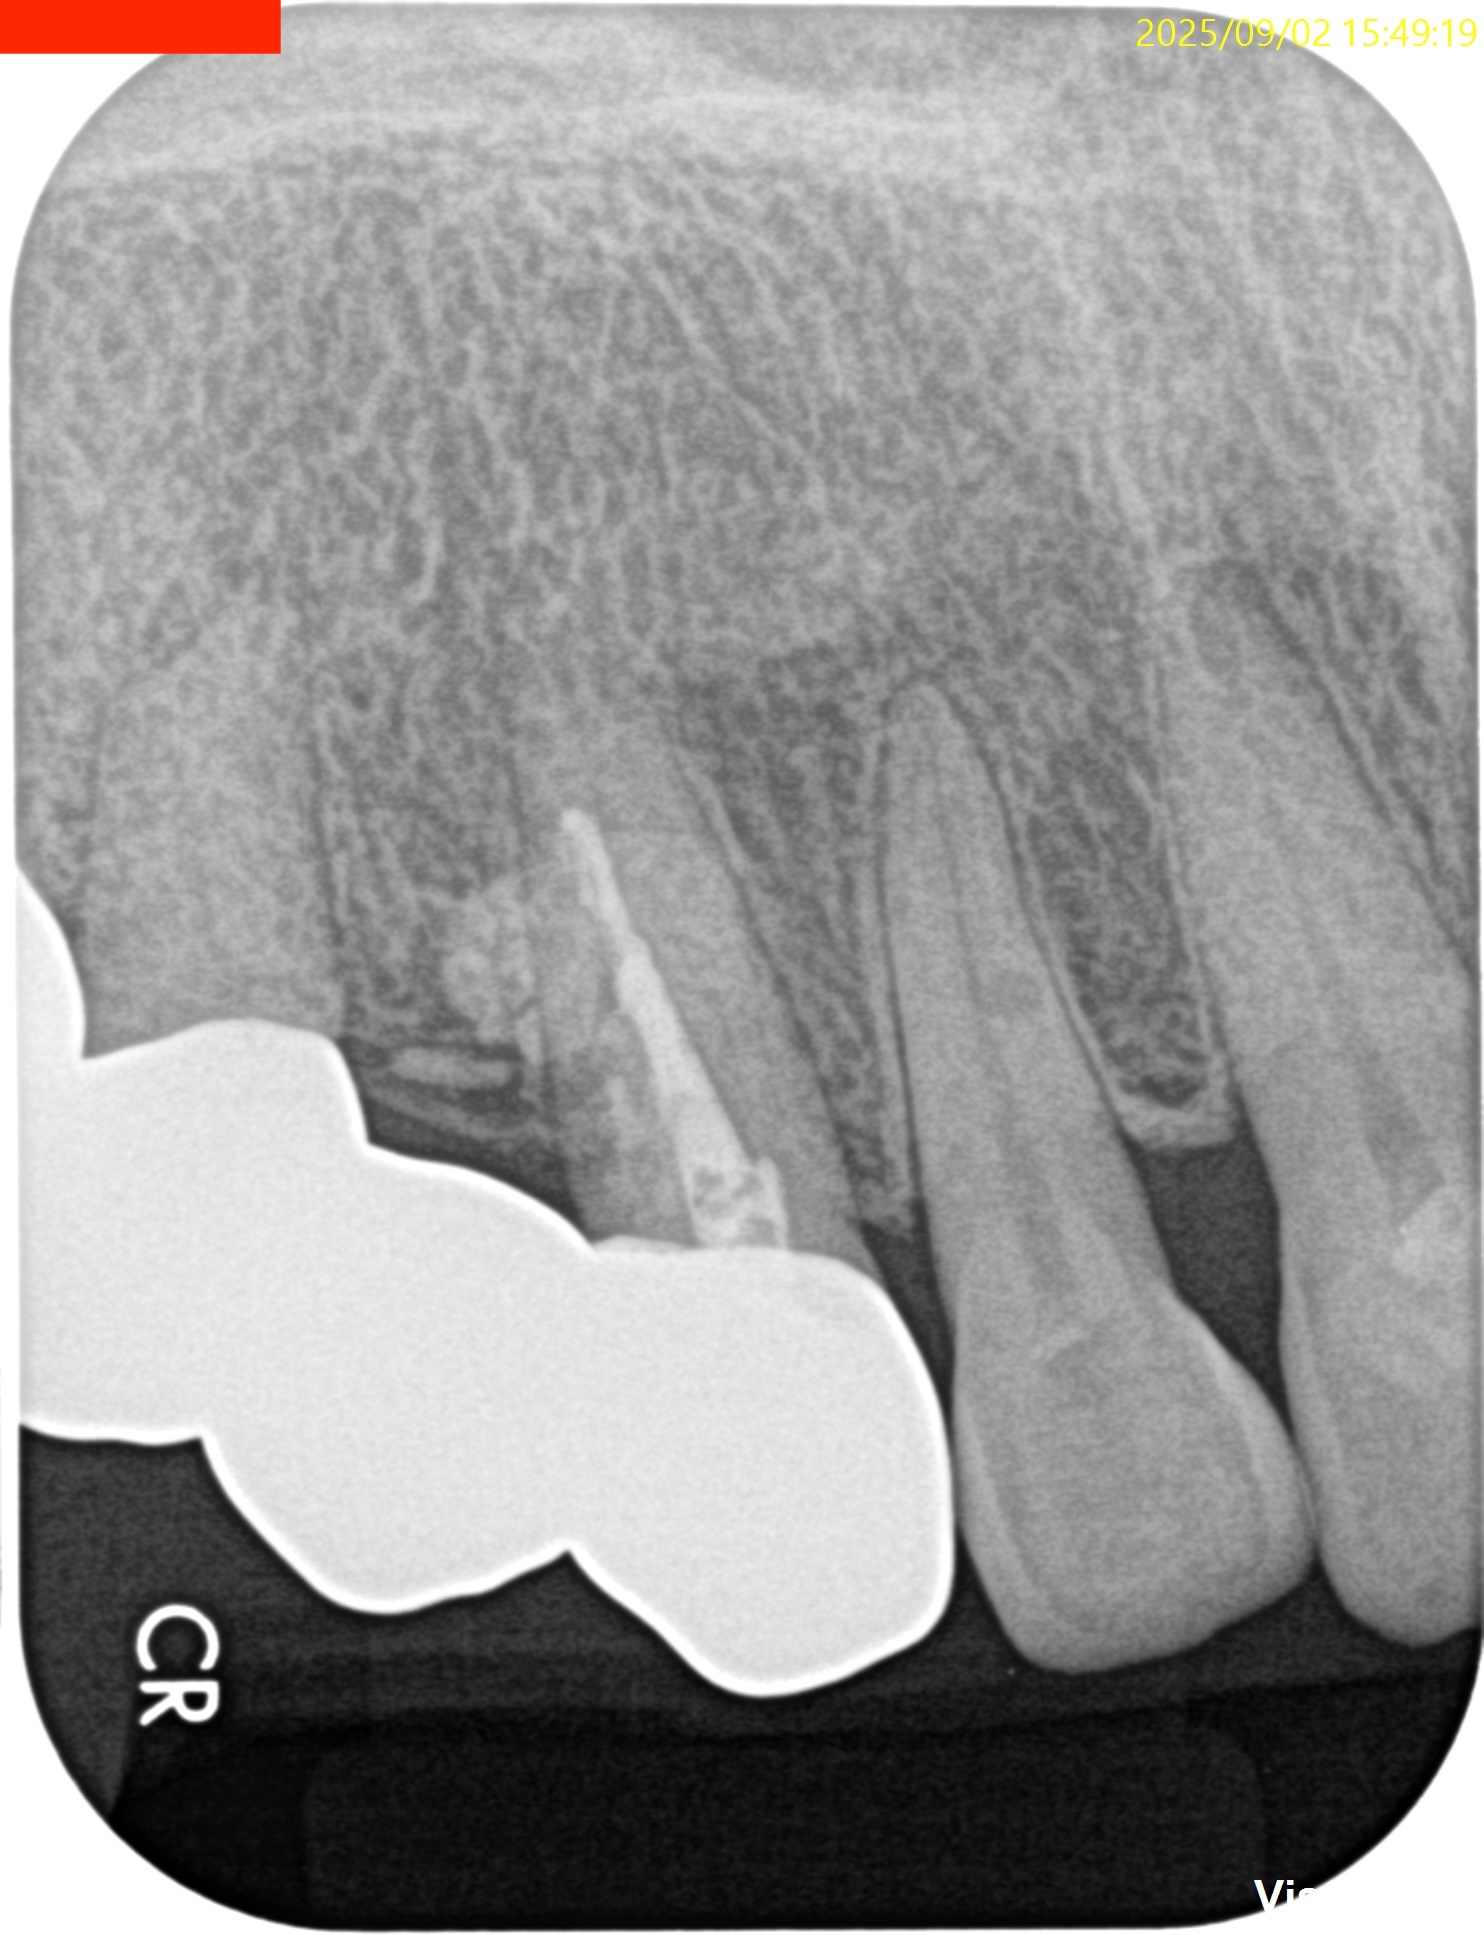

PA, CBCTを撮影した。

しょっぱい逆根管形成になったが主根管は確保されたので縫合して終了した。